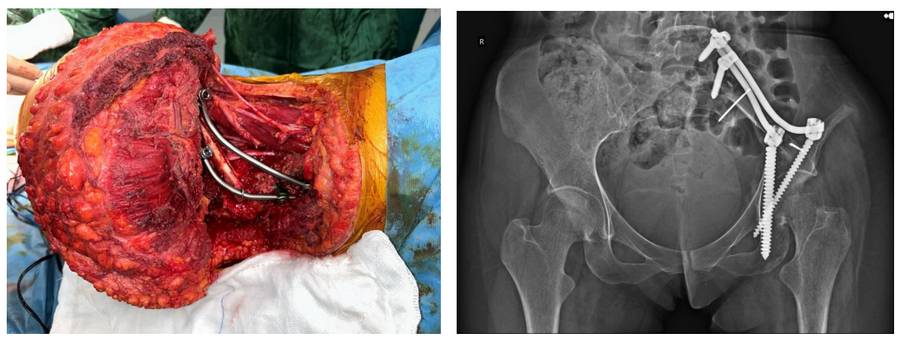

Hastaya internal hemipelvektomi sonrası fibula ve rod/vida ile rekonsrüksiyon işlemi uygulandı

Ameliyat Esnası ve Sonrası: İnternal hemipelvektomi sonrası fibula ve rod/vida ile rekonstrüksiyon işleminin klinik ve direk garfi görüntüsü